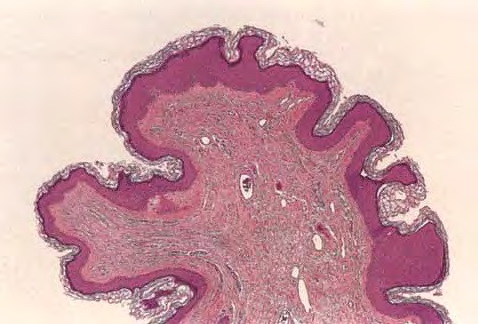

Fibroepithelial poly = البوليب الظهاري الليفي

Atlas of skin histopathology